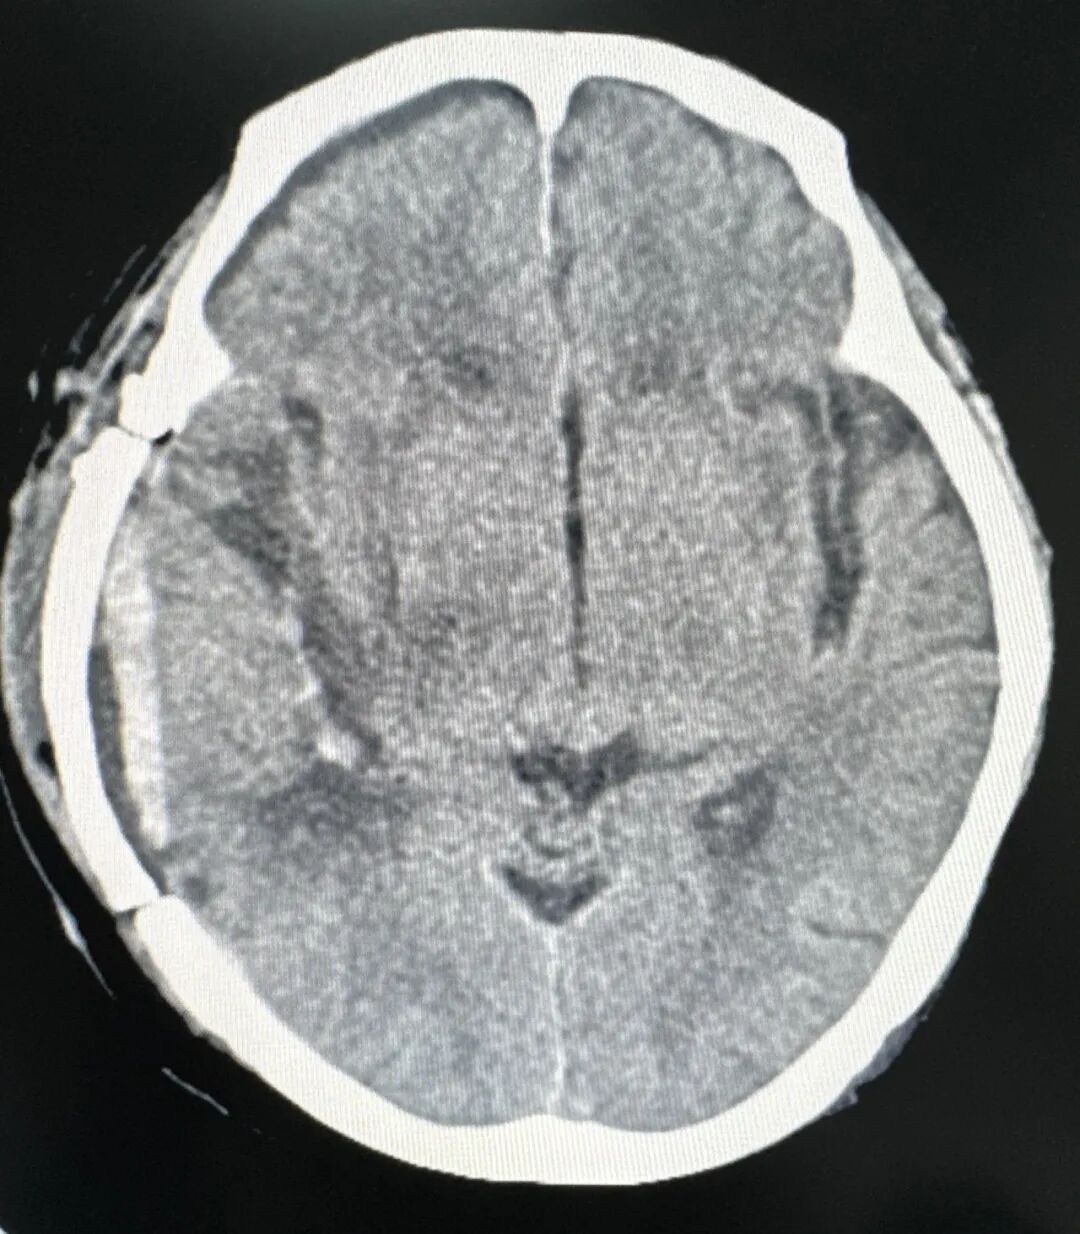

开颅右侧颞叶脑内血肿清除+颅内传感器植入

情况危急之下,神经外科许春旺主任会诊并与家属详细、充分地沟通病情后,迅速为老人开通绿色通道,在医护陪同下将患者迅速推入手术室,由神经外科许春旺团队行开颅右侧颞叶脑内血肿清除+颅内传感器植入术,历经2个小时手术顺利完成。